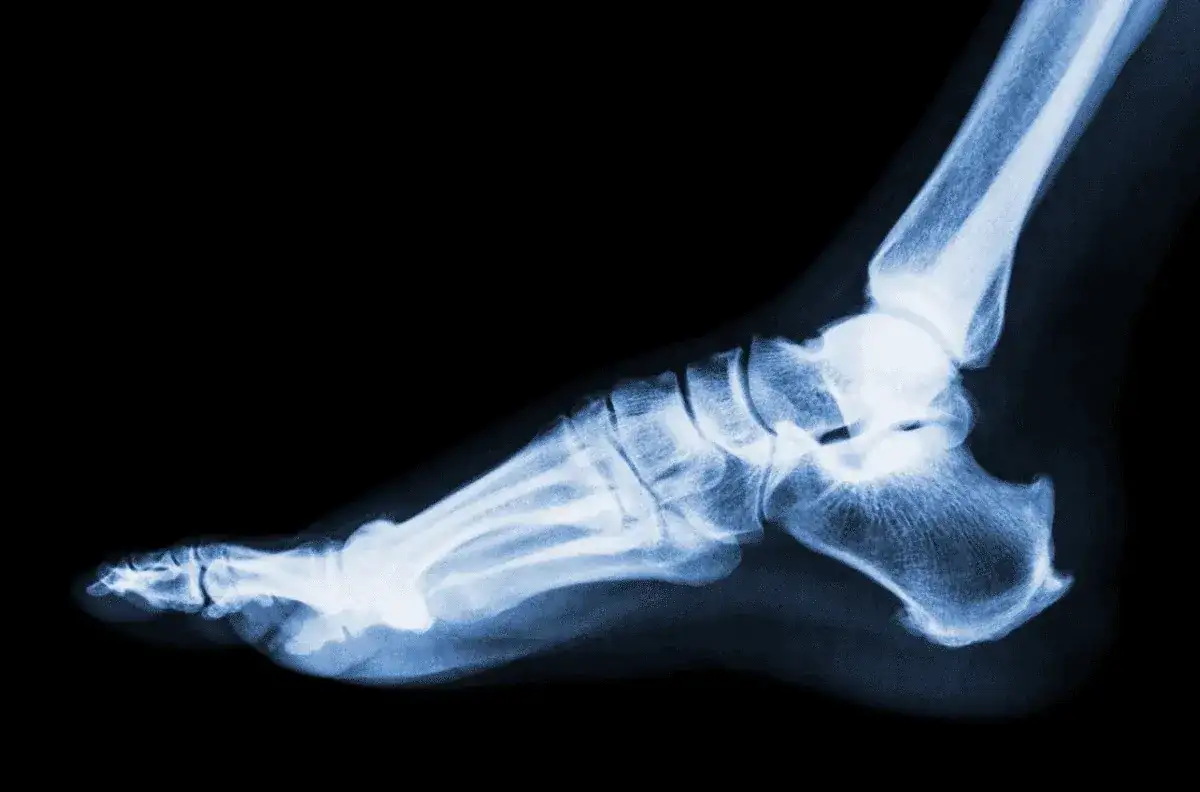

Ile czasu goi się skręcenie stawu skokowego? Poznaj kluczowe informacje

Ile czasu goi się skręcenie stawu skokowego? Dowiedz się, jakie czynniki wpływają na czas regeneracji i jak skutecznie przyspieszyć powrót do zdrowia.